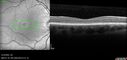

Stargardt Disease - Very Mild - 24 year old

This patient has 3 different ABCA4 mutations. His mother and sister have stargardts and his father has RP. His sisters images are also on Retinagallery.com